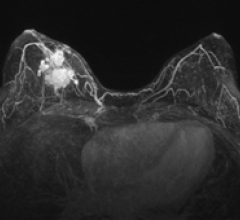

Despite decades of progress in breast imaging, one challenge continues to test even the most skilled radiologists ...

During RSNA 2011, Hologic will feature its Sentinelle Aegis Breast imaging and interventional software. This dedicated plug-in for the Aegis platform software offers powerful, real-time 4-D (3-D + time) image processing, combining speed, flexibility and dedicated breast MRI algorithms.

At RSNA 2011, Hologic will features its Selenia Dimensions 3-D breast tomosynthesis technology. It is designed to help clinicians in catching breast cancers earlier and in significantly reducing the number of unnecessary diagnostic work-ups.